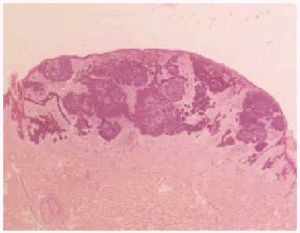

Se realizó extirpación de la tumoración y estudio histopatológico que demostró una lesión con características arquitecturales de benignidad, bien delimitada y simétrica localizada en la dermis (fig. 3). Estaba compuesta por células de aspecto basaloide, con ocasional formación de empalizada periférica. La inducción de la estroma originaba estructuras similares a las papilas foliculares. En la parte más superficial existía acumulación de pigmento melánico, tanto en los nódulos epiteliales como en melanófagos del estroma (fig. 4). El diagnóstico anatomopatológico fue de tricoblastoma pigmentado.

Fig. 3.--Panorámica histológica.

Fig. 4.--Epitelio con células basaloides y estroma con diferenciación folicular. En la parte más superficial se aprecian acumulaciones de pigmento melánico, tanto en los nódulos epiteliales como en los macrófagos del estroma.